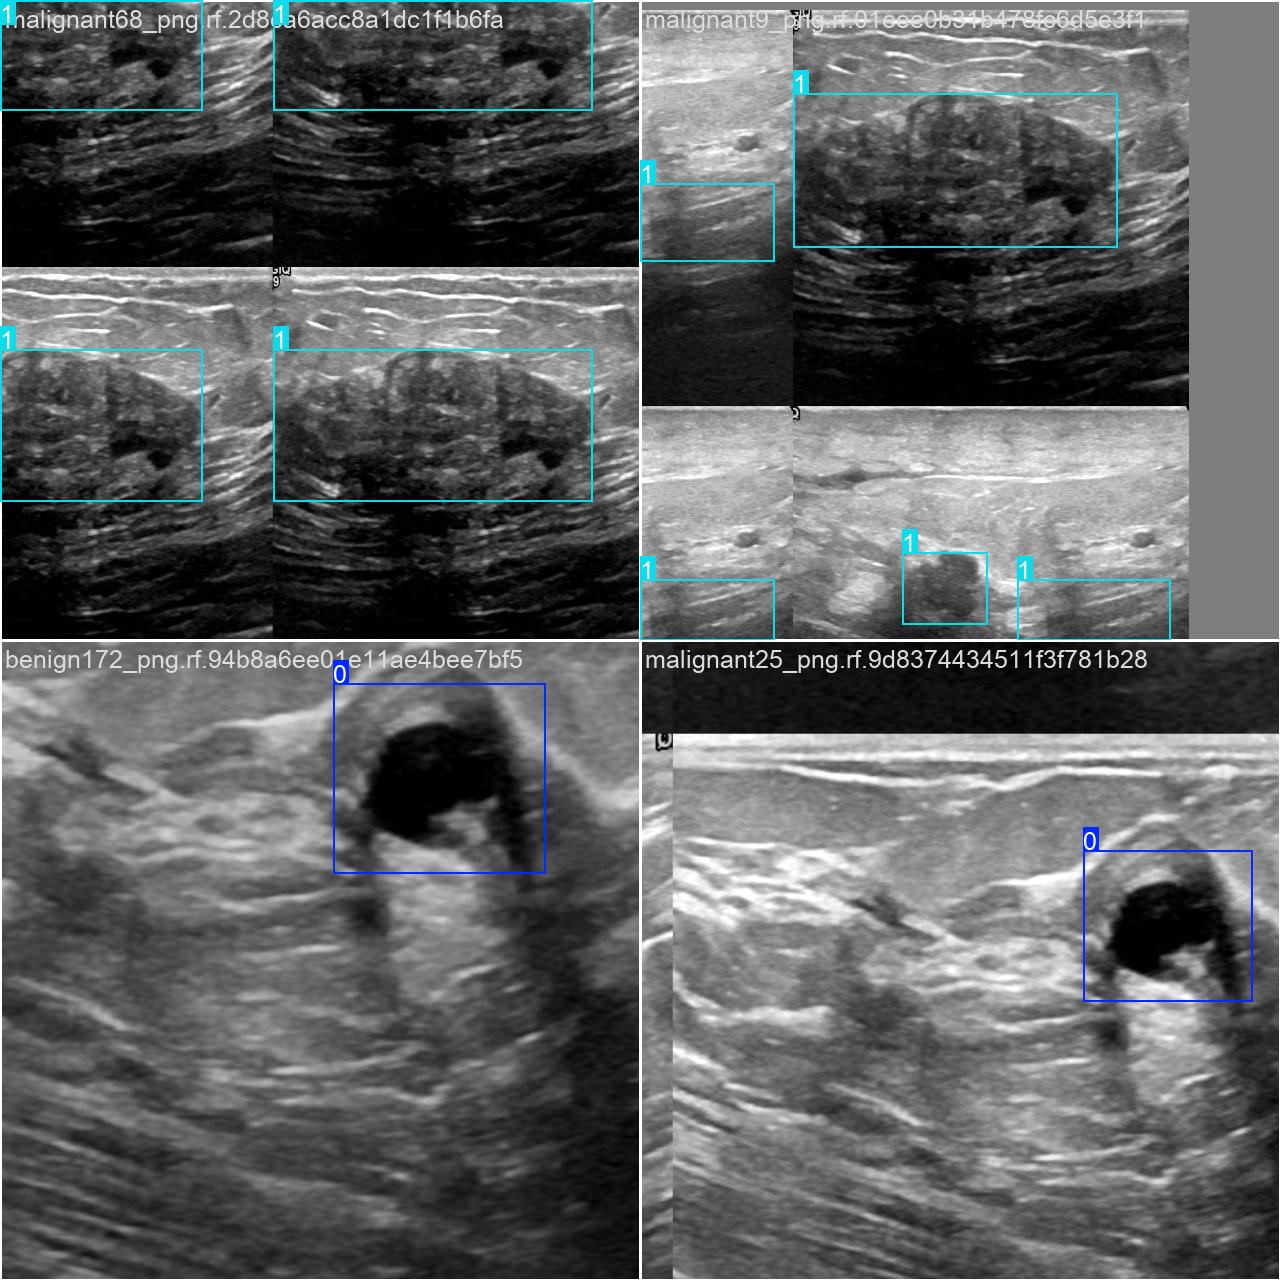

2.数据集准备与训练

本研究使用了包含各种甲状腺结节病症相关图像的数据集,并通过Labelimg标注工具对每张图像中的目标边框(Bounding Box)及其类别进行标注。然后主要基于YOLOv8n这种模型进行模型的训练,训练完成后对模型在验证集上的表现进行全面的性能评估及对比分析。模型训练和评估流程基本一致,包括:数据集准备、模型训练、模型评估。本次标注的目标类别为甲状腺结节病症,数据集中共计包含1863张图像,其中训练集占1452张,验证集占411张。部分图像如下图所示:

部分标注如下图所示: